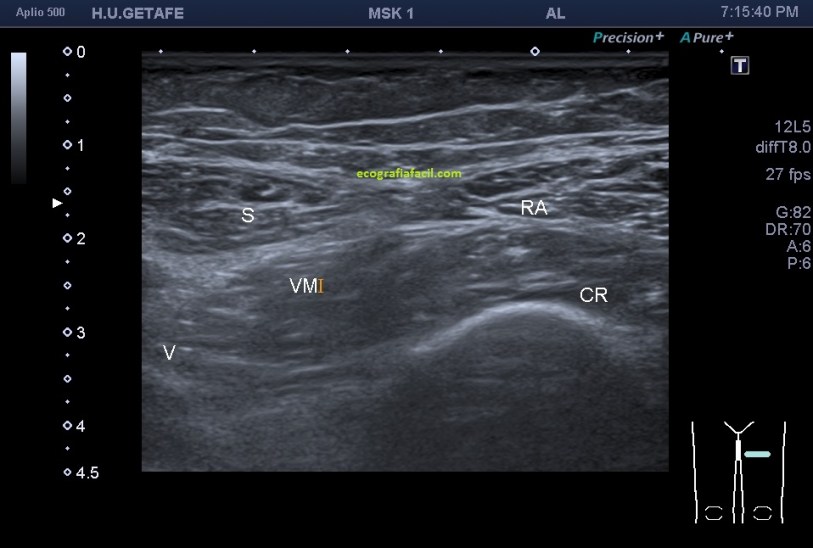

La anatomía donde situamos al Sartorio (S) en referencia al músculo vasto interno o medial (VM).